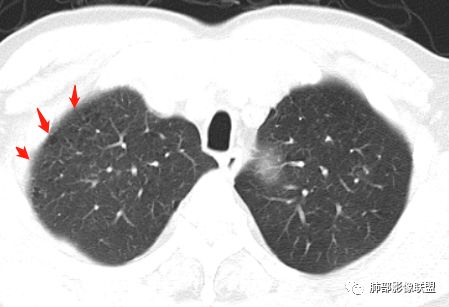

胸CT:左肺上叶前段实变,其周围及左肺上叶尖后段可见肺气肿背景下渗出性病变,病灶内可见支气管扩张,气道壁呈不规则增厚,双肺散在小结节状影;右肺下叶结节影,内可见空泡,边缘模糊,不规则。增强可见病灶内血管造影征,右肺门增大,纵隔淋巴结多发肿大。

左肺上叶大片混合网格磨玻璃影,边界清,边缘分叶膨隆,内支气管走行狭窄扩张,实变区边界清,上叶支气管管腔窄,心膈角淋巴结肿大,考虑肺炎型肺癌—腺癌。左肺下肺门结节,边缘膨隆,突入中间段及下叶支气管腔,背段支气管阻塞,周围少量小花小草,考虑鳞癌。右下叶外侧基底段结节,边缘有膨隆,有血管牵拉进入,上缘支气管贴边,考虑肺癌,性质?

晨读:左肺上叶大片实变影,周围可见磨玻璃影,小叶间隔增厚,部分支气管扩张,右肺下叶小结节,形态规则,边缘光滑,周围模糊晕征,中年男性,病史五天,白细胞正常,考虑NTM,奴卡,鉴别肺癌。

薏米:老年男性,发热,咳嗽5天,胸痛2天,平素慢性咳嗽,咳痰10年,未系统诊治,基础糖尿病史,此次以急性发病为主,白细胞正常,CRP增高,IGE增高,CEA轻度增高,左肺上叶散在片状密度增高影,边界清楚,小叶间隔增厚,内有磨玻璃影,部分支气管壁增厚,部分有扩张,部分有近段粗细不均,少许气囊,右肺下叶可见一结节影,有凹陷,有膨隆,似有结节感,综合考虑左肺上叶考虑黏液性腺癌,鉴别曲霉,抗感染后复查:右肺下叶恶性。

患者中老年男性,发热,咳嗽5天,胸痛2天。慢性咳嗽,咳痰10余年,未目前出现活动后胸闷气短,有基础糖尿病、高血压病史,查白细胞正常,CRP增高,IGE增高,CEA轻度增高。胸部CT:左肺上叶片状密度增高影,边界清楚,内见小叶间隔增厚,呈蜂窝网格状,内有磨玻璃影,部分支气管壁增厚,部分有扩张,部分有近段粗细不均;右肺下叶可见一结节影,有凹陷,有膨隆,似有结节感。综合考虑恶性病变,腺癌可能大,鉴别结核。

老年男性,糖尿病病史,crp及ige明显增高,cea轻度增高。影像:左肺上叶前段网格状高密度影,部分实变,部分前段支气管走形僵直。右肺下叶背段近肺门处及右肺下叶外侧基底段各见一枚结节,可见浅分叶,外侧基底段结节可见空泡。纵隔多发淋巴结肿大。综合考虑:肺癌,粘液腺癌?

患者中老年男性,发热,咳嗽5天,胸痛2天。慢性咳嗽,咳痰10余年,目前出现活动后胸闷气短,有基础糖尿病、高血压病史,查白细胞正常,CRP增高,IGE增高,CEA轻度增高。胸部CT:左肺上叶片状密度增高影,边界清楚,内血管穿行,呈蜂窝网格状,内有磨玻璃影,部分支气管壁增厚,部分有扩张,部分有近段粗细不均;右肺下叶可见一结节影,有凹陷,有膨隆,似有结节感,右侧肺门淋巴结肿大,纵隔多发淋巴结肿大、部分伴有钙化。综合考虑恶性病变,左上肺粘液腺癌可能,右下肺小细胞癌?两源论考虑:左上肺粘液腺癌或粘膜相关性淋巴瘤?右下肺结核球伴肺门淋巴结肿。

左上肺的病灶是间质性病变,呈铺路石征。

左肺上叶病灶长轴与支气管走形一致,提示沿支气管分布病变,倾向于炎性,大家可能怀疑这个病例是来源于胸膜下为主的,胸膜下来源首先整体是来源于胸膜下,与胸膜下之间没有间隙,而这例与胸膜下有间隙。而且这个病变是沿支气管朝外蔓延的,而胸膜下来源的是朝内蔓延的,唯一给我们错觉的是靠近纵隔胸膜这个地方有问题。但是靠近纵隔胸膜这个位置实变不是靠近胸膜实变,它边缘收缩的,没有膨隆的迹象。我们看到里面支气管直达远端稍扩张,是以中央间质为主、小叶间隔朝外蔓延,有间质也有实质病变,走向是沿中央间质方向走的,我个人倾向炎性病变。    问题是右下叶病灶怎么解释?右隔上、右肺门各有一个结节。这个病人有急性咳嗽、胸痛的病史,还有糖尿病病史,周围渗出比较明显,应该警惕炎性病变,要警惕克雷伯杆菌、结核、金葡菌霉菌,因为糖尿病人经常好发这些病菌感染。那么右下叶病变怎么考虑?能不能一元论?    左肺病灶是一个急性渗出为主的病变,一个急性感染的迹象;右肺下叶背段结节,没有看到支气管,增强图支气管壁增厚,局部小结节,呈分叶状,支气管堵塞,没有粘液栓样指套样改变,但是里面有强化,我倾向于癌,其次待排结核。我还是倾向于癌的可能性,恶性可能性大一些,可惜我看不到支气管腔内。还考虑有没有淀粉样变性的问题,弥漫钙化灶最常见的一个是结核,另一个是淀粉样变性。叶段支气管壁有弥漫增厚的迹象。所以淀粉样变性跟结核都要考虑。

鳞癌起源于支气管粘膜,是气道中最常见的恶性肿瘤,易造成支管壁增厚,并突入腔内形成结节,造成狭窄、阻塞或截断;早期鳞癌表现为沿支气管生长的梭形结节或局限性增厚,辖区内常出现阻塞性炎症,这样的病灶赢多平面重建并仔细观察支气管改变;如果有支气管壁偏心性增厚伴管腔狭窄或腔内结节形成,都要想到早期鳞癌的可能性,复查或内窥镜检查是必要的。

鳞癌好发于中老年人,与吸烟关系密切,如果发现不易吸收的,或同一部位反复无常局限性肺炎,我们应当仔细观察支气管壁的病变除外阻塞的可能;该病例右肺下叶背段及左肺上叶支气管有肿块及管壁的增厚,应当想到恶性可能。

2.左肺上叶大范围高密度影,几乎占据整个肺叶,没有体积改变,尽管小叶间隔显示明显,但初诊还是首先会想到社区肺炎,尤其是结合患者有发热及左侧胸痛的临床表现。

会是粘液腺癌吗?如此大范围,又在上叶,周围却未见向外飘散的结节影,难以想象。